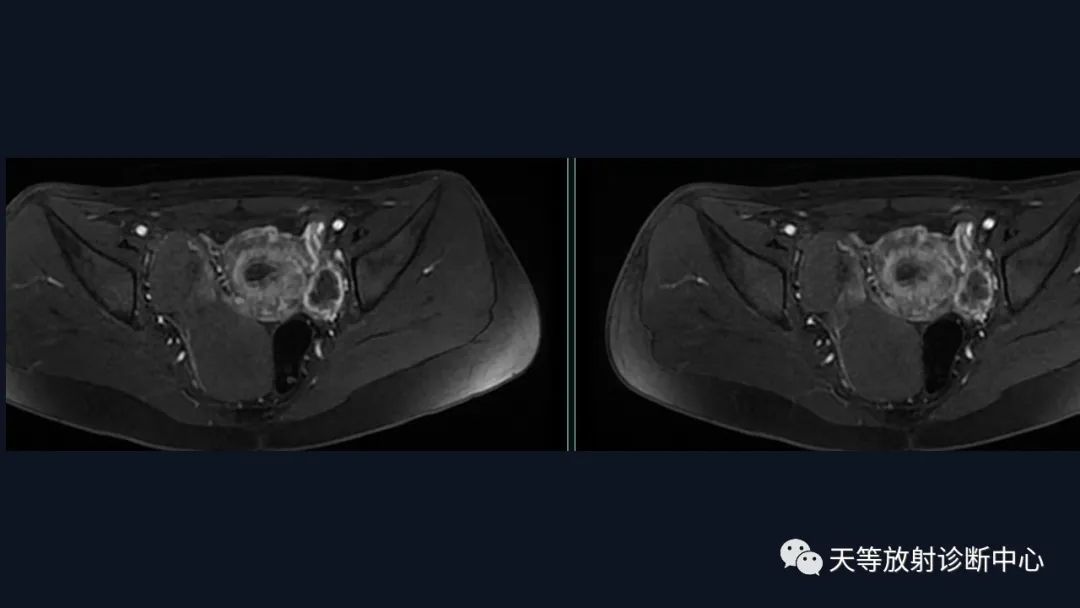

盆腔区右侧附件区见不规侧多发囊性信号肿块影,大小约104mm×37mm×64mm,边界清晰,大囊内信号均匀,相比于肌肉,T1WI呈稍高信号影,T2WI压脂序列呈高信号影,DWI呈高信号,肿块边缘区域尚见多发不同信号结节状囊性信号灶。另外左侧附件区见管状结构及结节状异常信号影,彼此相连,T1WI呈低信号,T2WI稍高信号,DWI呈稍高信号,边界清楚,较大结节直径约30mm。动态增强扫描,右侧囊性肿块见薄壁强化,囊内成分未见强化,而其旁部分结节影明显强化;左侧病灶亦见薄环状强化,但囊壁较对侧病灶厚,囊内成分未见强化,周围边界欠清。

盆腔区右侧附件区见不规侧多发囊性信号肿块影,

边界清晰,大囊内信号均匀,相比于肌肉,T1WI呈稍高信号影,T2WI压脂序列呈高信号影,DWI呈高信号,肿块边缘区域尚见多发不同信号结节状囊性信号灶。

另外左侧附件区见管状结构及结节状异常信号影,彼此相连,T1WI呈低信号,T2WI稍高信号,DWI呈稍高信号,边界清楚,较大结节直径约30mm。

动态增强扫描,右侧囊性肿块见薄壁强化,囊内成分未见强化,而其旁部分结节影明显强化。